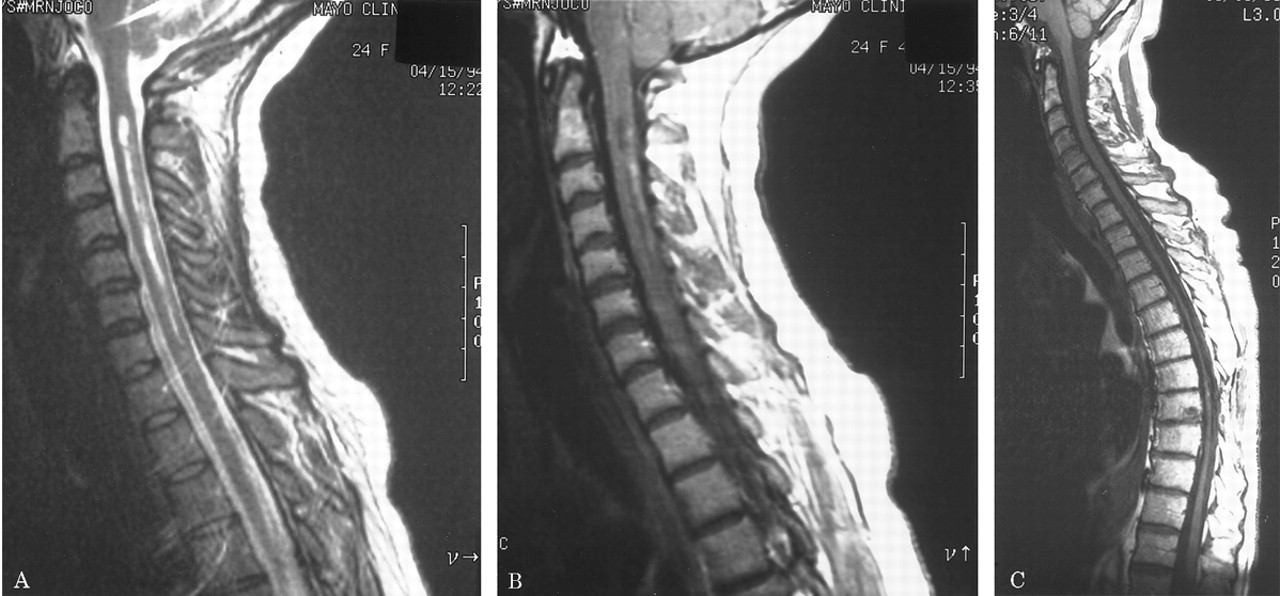

MRI:大脑。

特征典型的或明显的动了图4。脑部核磁共振进行了28 patients-27复发和1单相。中间间隔从第一个索引事件最初的大脑核磁共振是7.5个月(范围0.5 - 194)。视神经增强被认为在5 6例(83%)在2周内学习的一集。大脑实质是正常的在22个28初始扫描(79%);只有3 28(11%)满意的标准徽章等。10女士三个病人增加了T2信号在相邻的髓质纵向广泛的上颈椎脊髓损伤(见图4中,C和D)。

图4。选择先生大脑的图像。(A)扩散增强视神经交叉的gadolinium-enhanced t1日冕图像。(B)几室周的病变中看到一个病人在t2加权图像轴。(C和D)损伤扩展的吻侧颈绳在髓质gadolinium-enhanced t1矢状轴向和t2加权图像。

十六个复发患者多个大脑核磁共振;最初的扫描是正常14。后续核磁共振成像显示,7仍然正常(第一个和最后一个MRI的平均时间间隔,11个月;范围1 - 39)6开发了非特异性异常,不符合标准的徽章等。10女士(平均间隔23个月,范围3 - 85),和1个病人“转换”来满足女士标准103个月后。